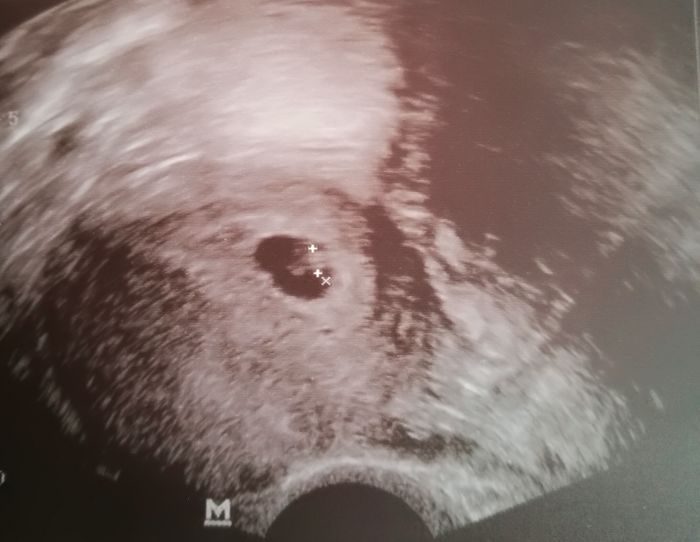

Vse je v poradku, srdicko boucha, velikost taky odpovida od vynechane menstruace, termin mam konec rijna.Hned jsem si rekla o fotecku. Chlap bude mit radost, ze tam nejsou dve.

6+2 a kulihrasek ma 3,4mm

Jááj, tak to je opravdu milimetřík!!! :-D já byla na 1. kontrole 7+0 a to už měl 9,5mm :-D Je úplně neuvěřitelné, že v něčem takovém už funguje i tep. To je prostě neskutečný zázrak! :-D